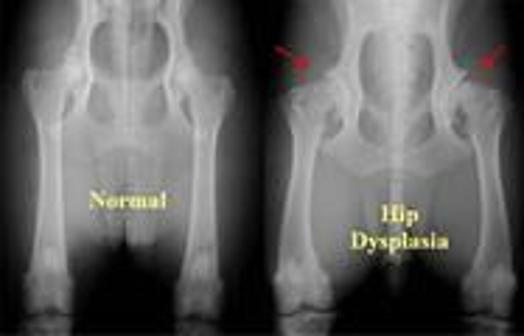

genetik bozukluk scottish fold ve kalca dizplazisi beyaz pati veteriner klinigi